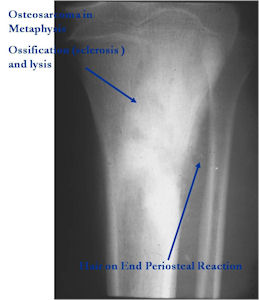

Radiographic Presentation

Plain X-rays:

- Geographic, circumscribed lesion usually around 5cm in size.

- There may be expansion of bone, cortical thinning and cortical breakthrough. A soft tissue mass may accompany this lesion but the soft tissue component is usually contained by the periosteum.

- The periosteum remains intact around the soft tissue component. Might need a CT scan to detect the subtle calcification (Egg Shell Rim of Calcification) associated with an intact periosteal reaction

- The lesion may be entirely radiolucent but usually shows some degree of mineralization. Mineralization may appear stippled like cartilage but do not see chondroid pathologically. Mineralization is sometimes better detected on a CT scan rather than an x-ray.

- Usually less surrounding sclerosis than an osteoid osteoma.

- Arise from the Diaphysis (75%) more commonly than Metaphyseal (25%)

- 4 cm to 6 cm in size

Aggressive Osteoblastoma vs. Osteosarcoma

Osteosarcoma:

- Cellular atypia

- High mitotic rate

- Atypical mitotic figures

- Abundant lacelike osteoid

- Permeative growth into adjacent bone and soft tissue

- Presence of neoplastic cartilage

- No peripheral shell of reactive bone